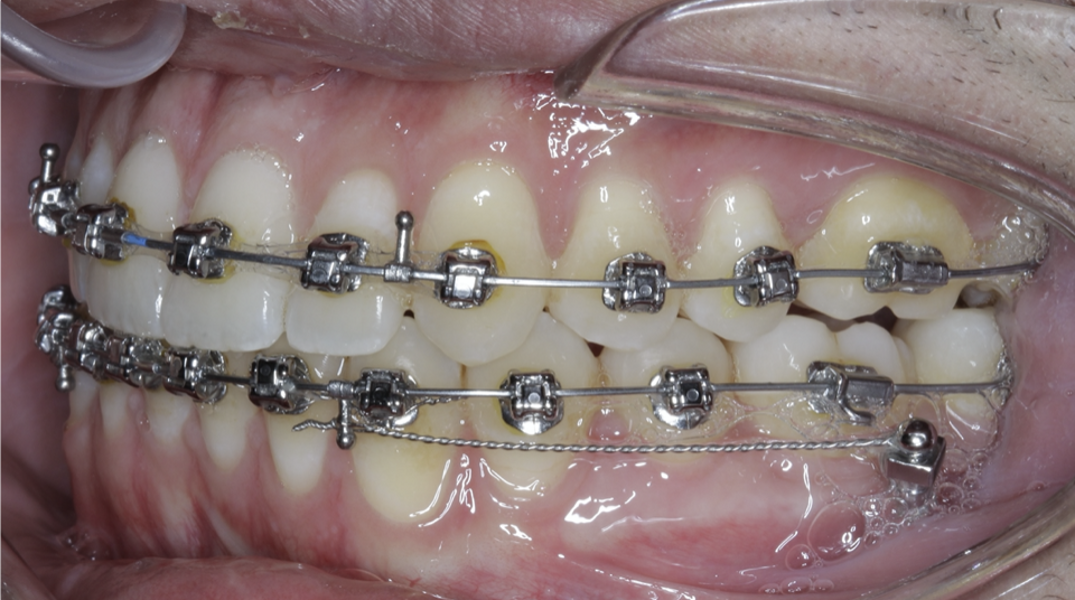

New Age orthodontics and orthopaedics with temporary anchorage devices